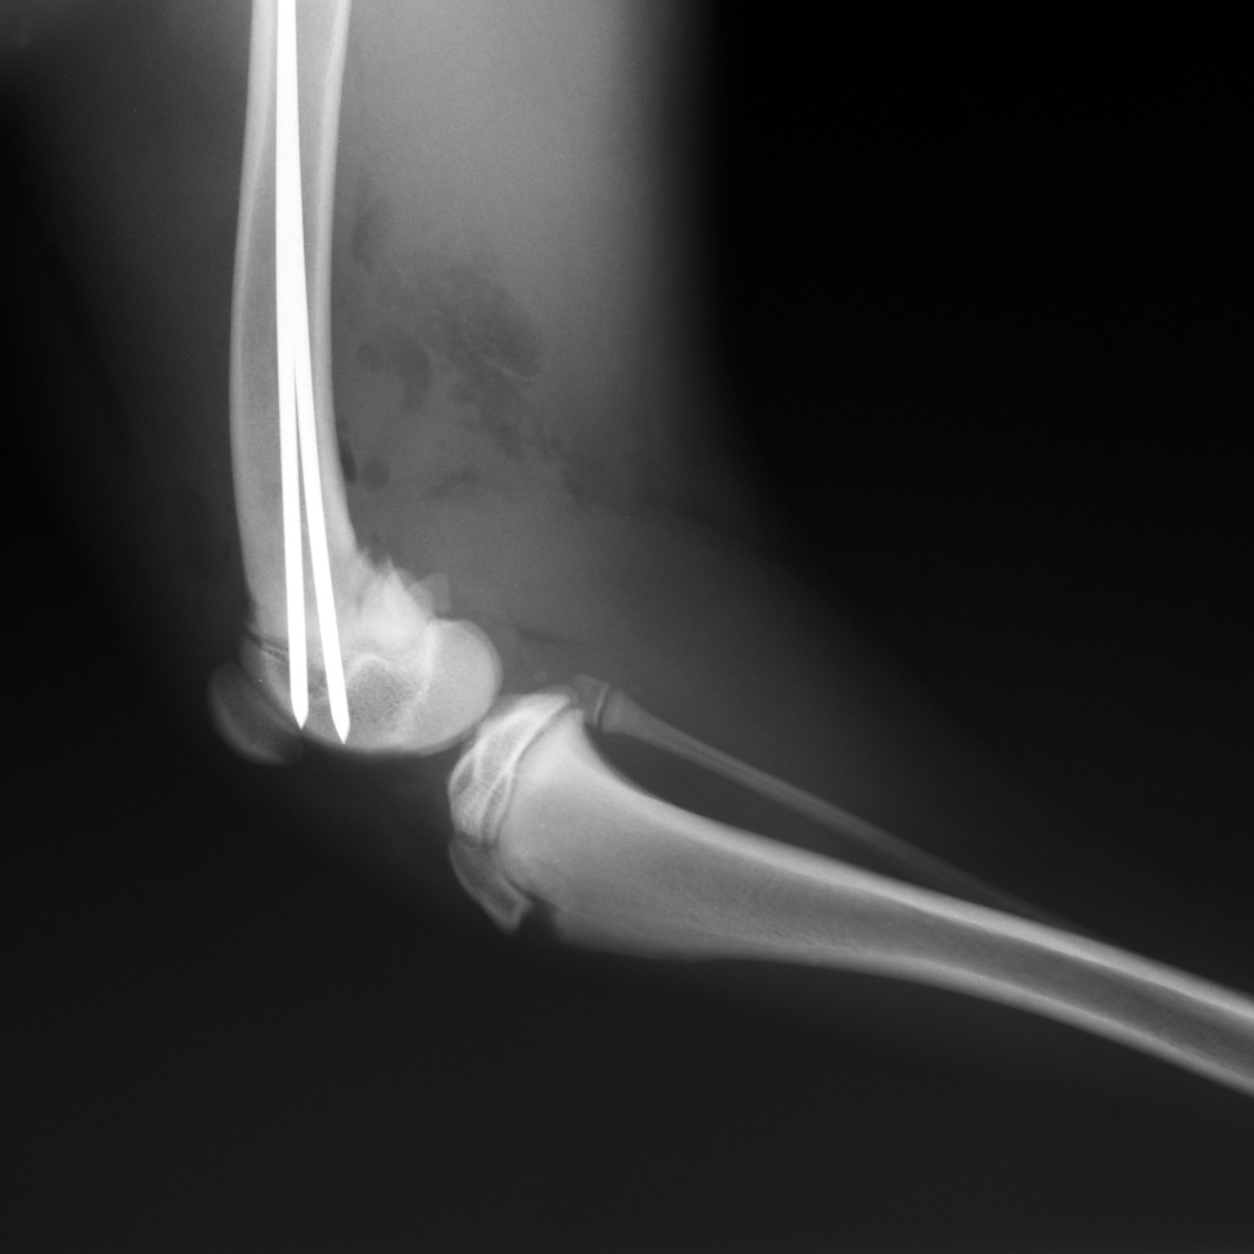

X-rays can be used to detect a variety of ailments in animals including arthritis, tumors, bladder and kidney stones, and lung abnormalities such as pneumonia. They are also used to evaluate bone damage, the gastrointestinal tract, respiratory tract, genitourinary system, organ integrity, and even identify foreign objects that may have been ingested. Dental radiographs help distinguish healthy teeth from those that may need to be extracted, and identify any abnormalities beneath the gums including root damage, tumors, and abscesses. In some cases, we may need to sedate your pet or use short-acting general anesthesia.